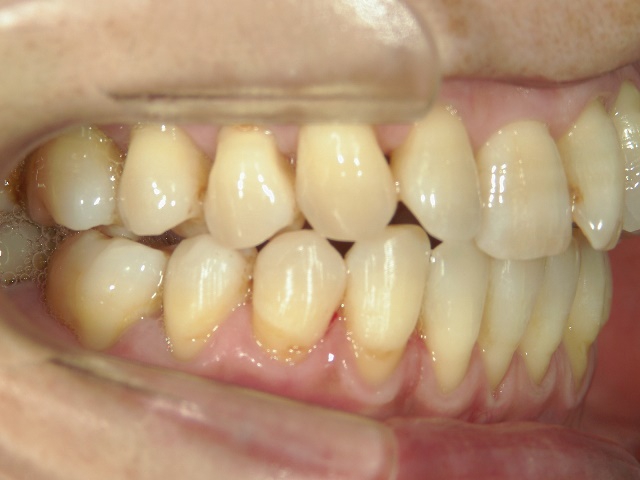

矯正歯科 治療前矯正歯科 治療前

矯正歯科 治療前

no.12_5333_治療前_左.jpgno.12_5333_治療前_正面.jpgno.12_5333_治療前_右.jpg